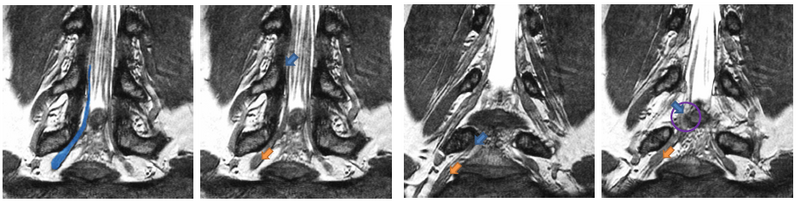

We show four slices of an example High-Resolution MR scan. The blue outline in the first figure shows a manual segmentation of a nerve for reference. All arrows point to the same nerve bundle. Blue arrows show examples of poor contrast between the nerve and the surrounding tissue; orange arrows indicate the thickening of the neural tract into a ganglion.